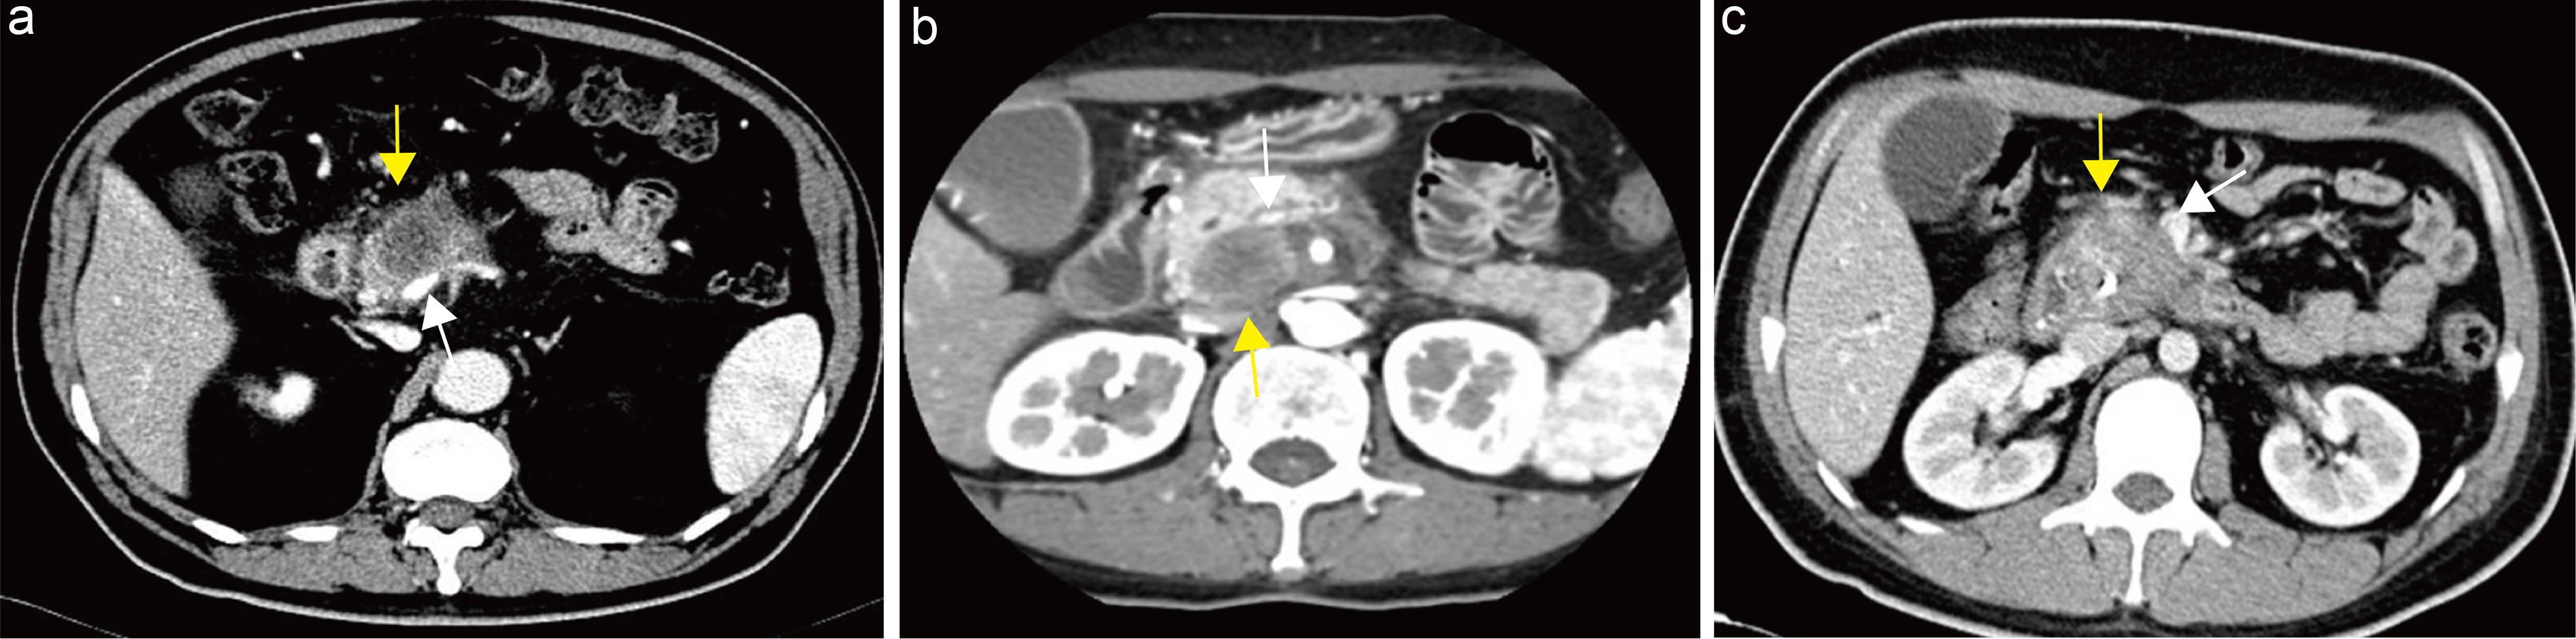

Explanation: Pancreatic cancer originates from ductal epithelial cells and can obstruct the pancreatic duct, causing upstream retention of pancreatic juice and cystic dilation, forming retention cysts lined by ductal epithelium on pathology.101 When intraductal pressure increases or the pancreatic duct ruptures, pseudocysts may form; these can also develop secondary to obstructive acute pancreatitis. Pseudocysts consist of fluid collections surrounded by non-epithelial tissue within or adjacent to the pancreas.102 Differentiation between retention cysts and pseudocysts requires pathological examination; radiologically, they are often difficult to distinguish, both typically presenting as unilocular cysts with variably thick walls, commonly located in the pancreatic body or tail without obvious mural nodules.101 Studies have identified pancreatic cysts ≥5 mm as independent predictors for pancreatic cancer development.103 In patients with elevated CA19-9 and retention cysts, vigilance for small or isoattenuating pancreatic cancers nearby is warranted.50,104 This guideline recommends that when retention or pseudocysts are detected, they should be clearly reported with measurements of size and description of location (Fig. 6).

Pseudocyst formation secondary to pancreatic cancer.

Fig. 6  Pseudocyst formation secondary to pancreatic cancer.

Axial arterial-phase computed tomography (CT) image demonstrates a hypodense mass in the pancreatic body (white arrow) and an adjacent lower-attenuation lesion (yellow arrow) representing a pseudocyst. The measurement method is illustrated by the yellow line.